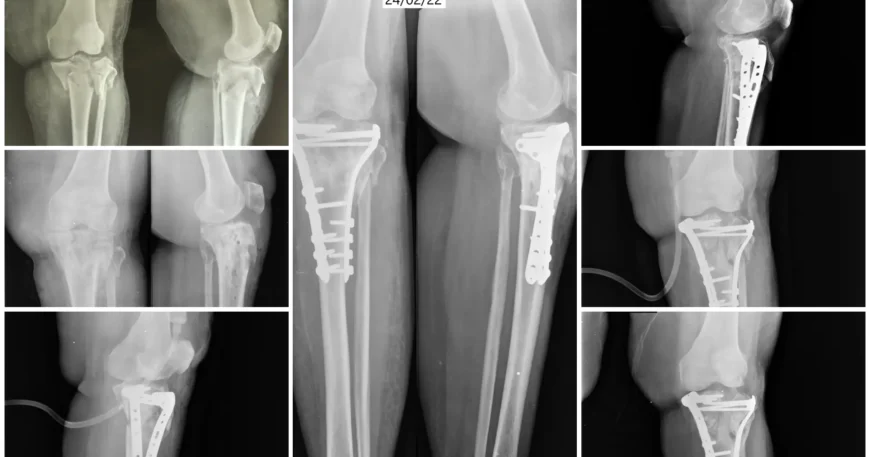

Clinical examination and imaging studies confirmed a Right Proximal Tibia Fracture involving both medial and lateral columns of the bone. Such fractures require precise anatomical reduction to restore joint alignment and maintain knee stability.

Open Reduction and Internal Fixation (ORIF) with Bicolumnar Plates and Screws

Mrs. Ananthamma underwent Open Reduction and Internal Fixation (ORIF) using bicolumnar plates and screws.

Anatomical realignment of both medial and lateral columns

Stabilization using dual (bicolumnar) plating technique

Rigid fixation with screws for enhanced stability

Bicolumnar fixation provides superior mechanical strength, especially in complex fractures involving both sides of the proximal tibia.

Good fracture alignment

Stable bone healing